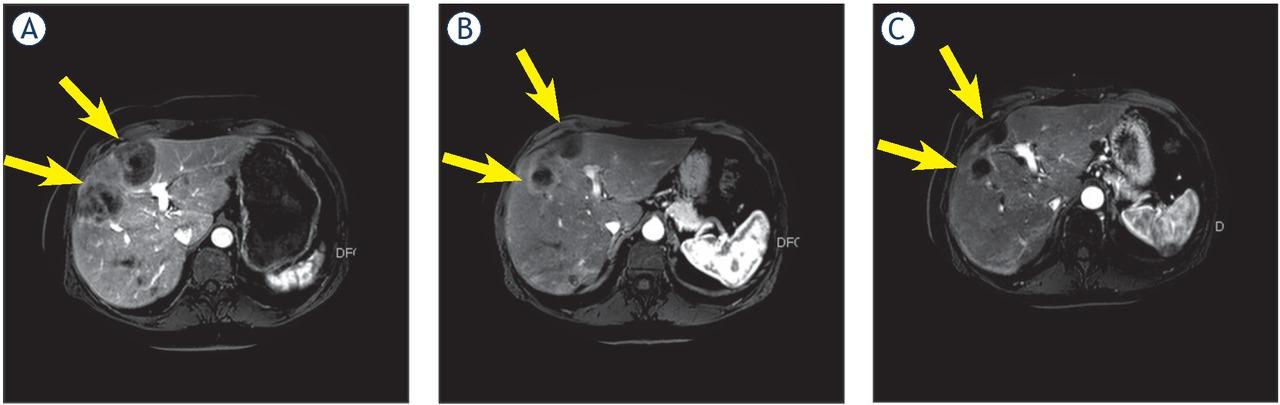

Figure 1